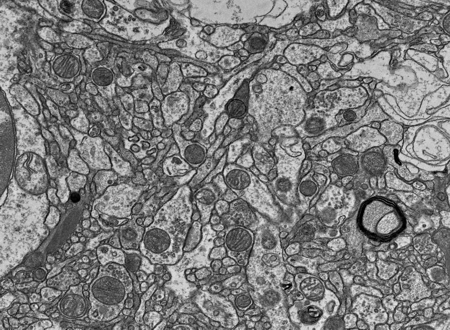

We measure our preservation quality in research cases at the nanoscale with cutting-edge volume electron microscopy.

Our Preservation Quality

FIB-SEM stack from the frontal cortex of a donated human research brain, that we preserved via perfusion fixation with 10% neutral buffered formalin after 4.5 hours of warm ischemia. This video shows sequential slices through the tissue, revealing the 3D structure of preserved neurons, axons, and other cellular structures.